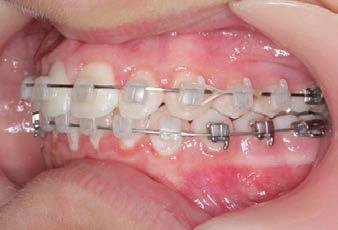

Carriere Motion 3D Appliance

Fastrack your orthodontic treatments. Save 6 months or more.

The SAGITTAL FIRST™ Philosophy is a time-tested approach that standardises, simplifies, and shortens Class II and Class III treatment times. It employs the Carriere Motion 3D Appliance to treat the AP dimension at the beginning of treatment before placing brackets or aligners. By resolving the most difficult part of treatment first, you can achieve a Class I platform in 3 to 6 months, shortening total treatment time by a minimum of 6 months1. You know how excited patients and parents become when you mention shorter treatment times.

CLASS II DIV.1 - Marra

PROVIDED BY: DR. LUIS CARRIÈRE

INITIAL - 4/4/18

PROGRESS 1 - 26/9/18 - Class I platform accomplished in 5.75 months with Motion 3D COLOR Appliance

PROGRESS 2 - 26/9/18 - Placement of the SLX 3D Clear Brackets

[CONTINUED ON NEXT PAGE]